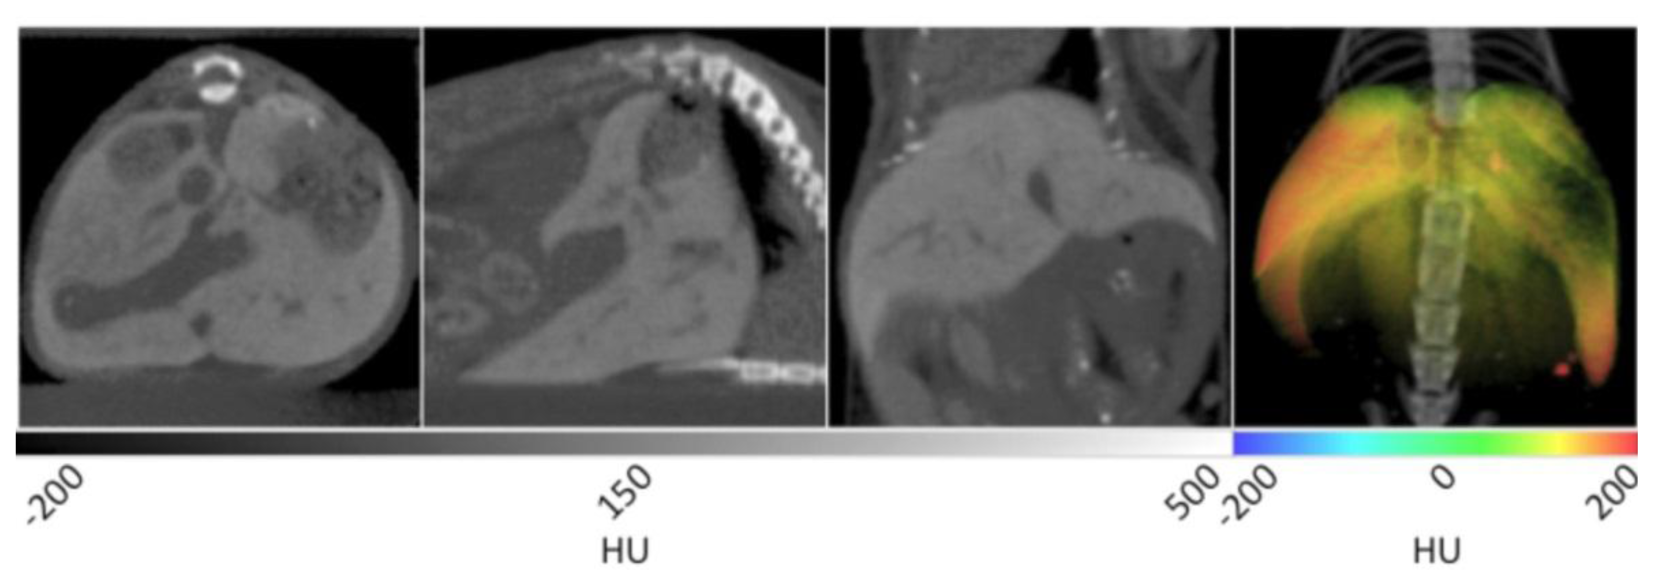

The slice data and a 3D reconstruction of an obese mouse (B6.V-Lep°B/J, male, 12 weeks old) are displayed in Figure 2. In the transverse view shown on the left, significant visceral fat deposits can be observed around the kidneys as lower density volumes owing to the decreased attenuation of adipose. In the sagittal view, more extensive subcutaneous fat deposits can be observed in addition to those in the abdomen. In the coronal view, fat deposits are seen around the kidneys, gastrointestinal tract and liver. The fat volume was segmented in a similar manner as the lungs using PMOD software, however values were bounded to −200 and −50 HU. Once the adipose tissue was segmented and allocated into an independent data set, it was false colored red and overlaid on the original CT to aid visualization. In the right frame of Figure 2, the 3D rendering displays the full extent of the spatial distribution of the fat deposits. Specifically, the extent of the visceral and subcutaneous adipose is highlighted, especially around the limbs and gut area. The segmented adipose tissue may be quantified in units of cm3, and divided by the whole animal volume to give a percent body fat value that may be monitored over time and under different experimental conditions.